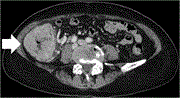

Incarcerated native orthotopic kidney through an inguinal hernia: a case report and literature review

Jisoo Kim and others

Journal of Surgical Case Reports, Volume 2023, Issue 7, July 2023, rjad378, https://doi.org/10.1093/jscr/rjad378